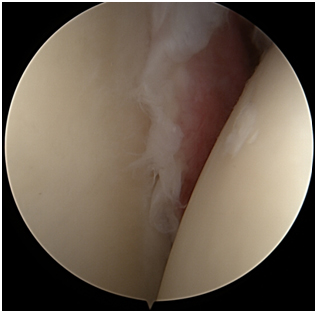

Η αρχική αντιμετώπιση της ασβεστοποιού τενοντίτιδας είναι συντηρητική και περιλαμβάνει μέτρα, όπως ξεκούραση, τροποποίηση δραστηριοτήτων, αντιφλεγμονώδη φάρμακα, φυσικοθεραπείες, ενδυνάμωση, τοπικές εγχύσεις κορτιζόνης, και την τεχνική αναρρόφησης διπλής βελόνης – υπό καθοδήγηση υπερήχου. Αν ο/η ασθενής δεν ανταποκριθεί στα συντηρητικά μέσα, θέση παίρνει η επεμβατική θεραπεία της ασβεστοποιού τενοντίτιδας. Η τελευταία είναι η μόνη θεραπεία που αντιμετωπίζει ριζικά το αίτιο της ασβεστοποιού τενοντίτιδας. Αυτό γίνεται καθώς εξαλείφει τελεσίδικα τον αιτιολογικό παράγοντα πρόκλησης της φλεγμονής, που δεν είναι άλλος από την ασβέστωση (βλέπε διεγχειρητική φώτο ασβέστωσης).

Στην περίπτωση της εμμένουσας ασβεστοποιού τενοντίτιδας του ώμου, ο στόχος της αρθροσκοπικής επεμβατικής θεραπείας είναι να εξαλειφθεί το γενεσιουργό αίτιο του πόνου (ο βράχος μέσα στον τένοντα), αλλά και να καθαριστεί η φλεγμονή του θυλάκου και του τένοντα. Η αρθροσκοπική τεχνική θεραπείας της εμμένουσας ασβεστοποιού τενοντίτιδας του ώμου περιλαμβάνει την έκπλυση και πλήρη αφαίρεση της ασβέστωσης από το εσωτερικό του τένοντα. Στην περίπτωση μεγάλης ασβέστωσης, το κενό που μένει εντός του τένοντα μετά την αφαίρεση της ασβέστωσης (του βράχου), συγκλείεται με ένα ειδικό αρθροσκοπικό ράμμα (μινι ράμμα).